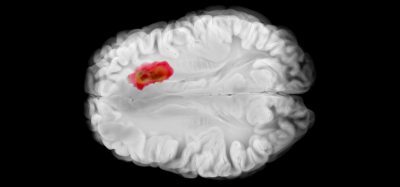

According to new research, the mitochondrial enzyme dihydroorotate dehydrogenase (DHODH) plays an important and previously unknown role in blocking a form of cell death called ferroptosis. The researchers, from the University of Texas MD Anderson Cancer Center, US, say that pre-clinical findings suggest targeting DHODH can restore ferroptosis-driven cell death, pointing to new therapeutic strategies that may be used to induce ferroptosis and inhibit tumour growth.

In GPX4-low cancers, brequinar effectively induced ferroptosis and suppressed tumour growth, but the effects were not seen in GPX4-high cancers. However, the combination of brequinar and sulfasalazine, a US Food and Drug Administration (FDA)-approved ferroptosis inducer, resulted in a synergistic effect to overcome high GPX4 expression and to block tumour growth.